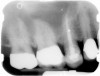

A Class IN maxillary bicuspid was previously restored with a fiber post and an all-porcelain crown (Figure 1). The forces of the oral environment resulted in fracture of the fiber post and crown failure. The remaining fiber post in the root was removed, and anti-rotational areas were prepared for a cast post (Figure 2). A gold cast post was constructed at a dental laboratory, using an indirect technique (Figure 3). A porcelain-fused-to-metal (PFM) crown was constructed with a bevel finish to provide a ferrule and reduce forces on the post (Figure 4 and Figure 5).

Figure 3  Cast post to restore the second bicuspid.

Figure 3

Figure 4  The cast post was cemented.

Figure 4